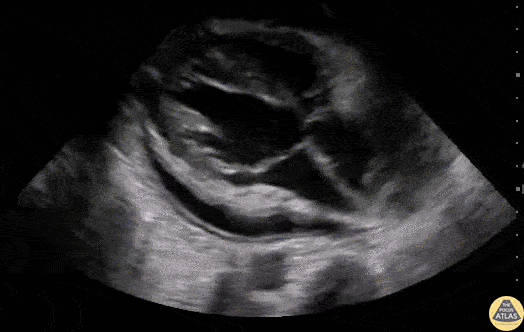

Pericardial Disease - Cardiac Tamponade

60 y/o M with metastatic lymphoma presented with SOB over 3 days. POCUS revealed a pericardial effusion that, along with his vital signs and clinical picture, altogether suggested pericardial tamponade. Notice the diastolic collapse of the right ventricle (as the mitral valve opens, the right ventricle free wall collapses). Mitral and tricuspid inflow velocities were also used as a surrogate for pulsus paradoxus. Dr. Stephen Alerhand - Mt Sinai Hospital, NYC